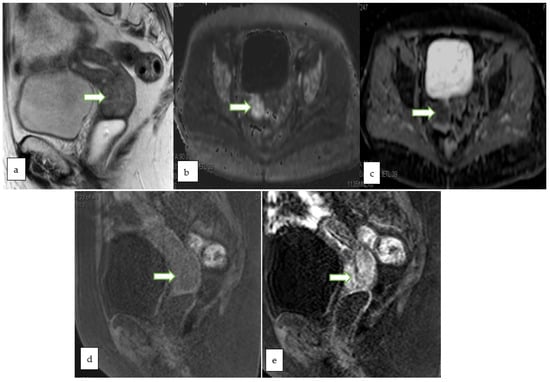

| O-RADS MRI Score | Risk Category | Positive Predictive Value for Malignancy | Lexicon Description |

| 2 | Almost certainly benign | <0.5% | Cyst: Unilocular- any type of fluid content - No wall enhancement - No enhancing solid tissue * |

| Cyst: Unilocular–simple or endometriotic fluid content -Smooth enhancing wall -No enhancing solid tissue | |||

| Lesion with lipid content ** - No enhancing solid tissue | |||

| Lesion with solid tissue showing dark signal on T2/DWI -Homogeneously hypointense on T2 and DWI | |||

| Dilated fallopian tube-simple fluid content - Thin, smooth wall/endosalpingeal folds with enhancement - No enhancing solid tissue | |||

| Para-ovarian cyst–any type of fluid - Thin, smooth wall +/− enhancement - No enhancing solid tissue | |||

| 3 | Low risk | ~5% | Cyst: Unilocular–proteinaceous, hemorrhagic or mucinous fluid content - Smooth enhancing wall - No enhancing solid tissue |

| Cyst: Multilocular-Any type of fluid, no lipid content - Smooth septae and wall with enhancement-No enhancing solid tissue | |||

| Lesion with solid tissue (excluding T2 dark/DWI dark) - Low risk time intensity curve on DCE MRI | |||

| Dilated fallopian tube - Non-simple fluid: Thin wall/folds - Simple fluid: Thick, smooth wall/folds - No enhancing solid tissue | |||

| 4 | Intermediate risk | ~50% | Lesion with solid tissue (excluding T2 dark/DWI dark) - Intermediate risk time intensity curve on DCE MRI - If DCE MRI is not feasible, score 4 is any lesion with solid tissue (excluding T2 dark/DWI dark) that is enhancing ≤ myometrium at 30–40 s on non-DCE MRI |

| Lesion with lipid content - Large volume enhancing solid tissue | |||

| 5 | High risk | ~90% | Lesion with solid tissue (excluding T2 dark/DWI dark) - High risk time intensity curve on DCE MRI - If DCE MRI is not feasible, score 5 is any lesion with solid tissue (excluding T2 dark/DWI dark) that is enhancing > myometrium at 30–40 s on non-DCE MRI |

| Peritoneal, mesenteric or omental nodularity or irregular thickening with or without ascites |